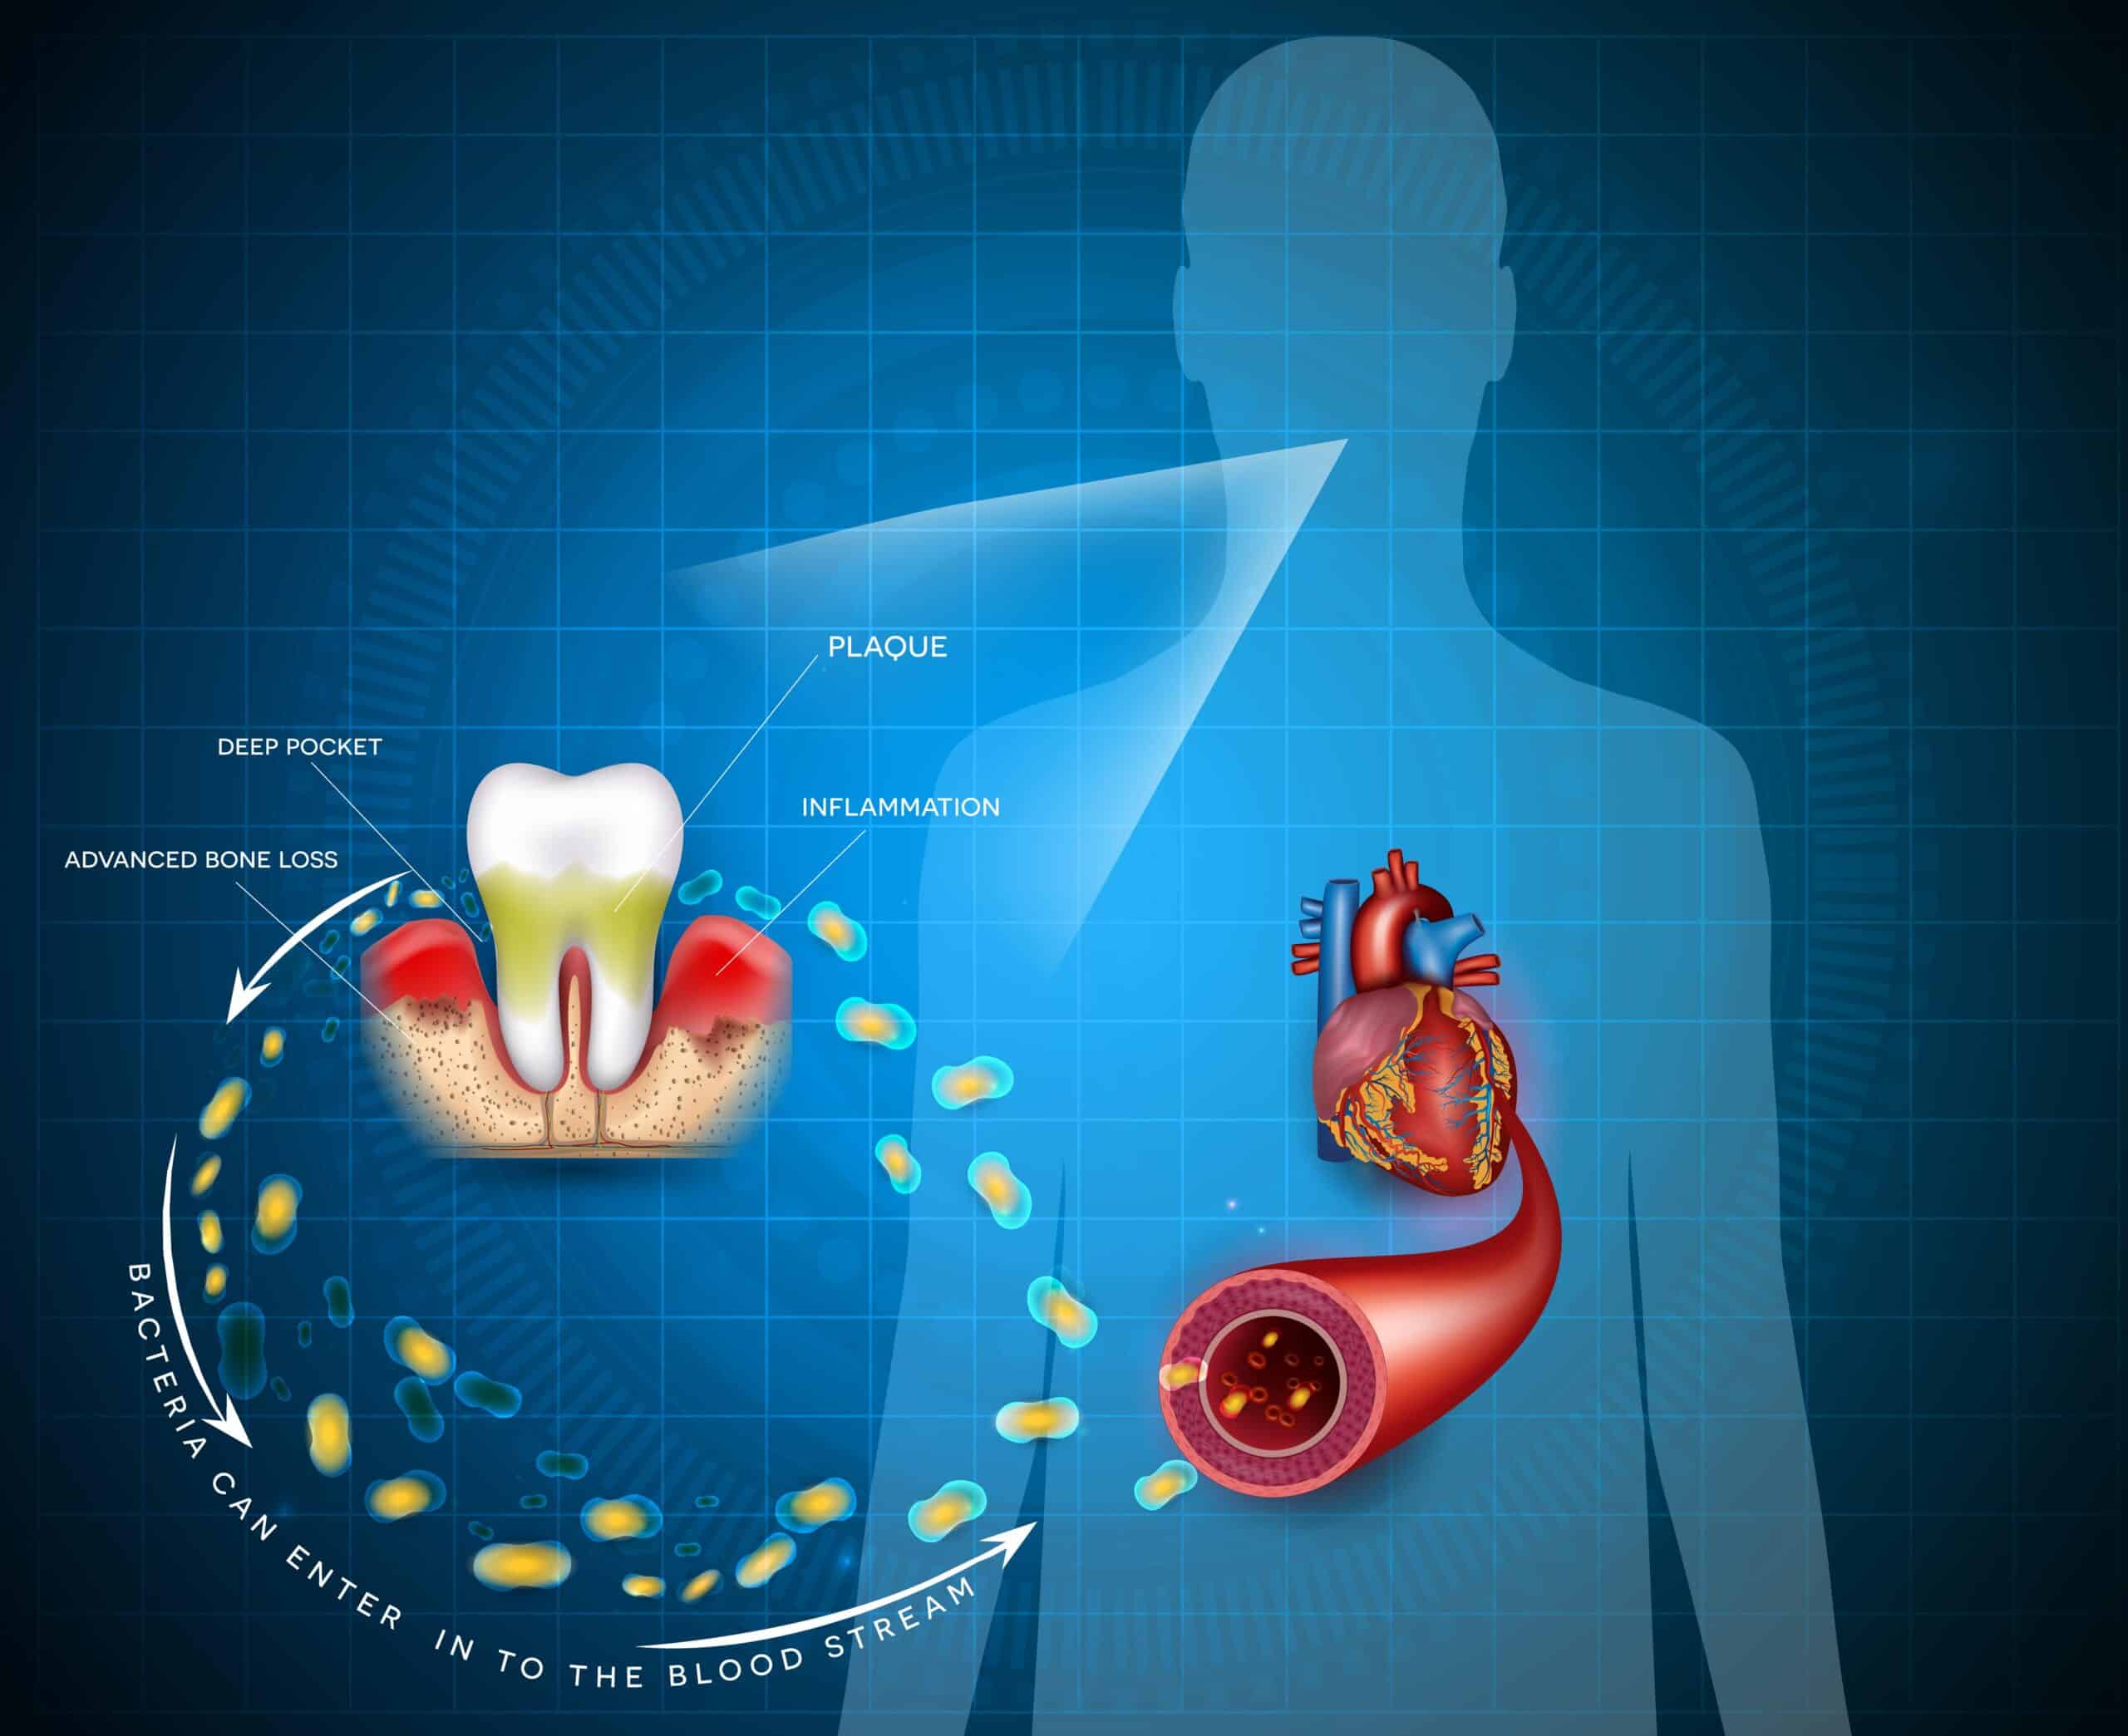

La parodontite : de graves conséquences pour la santé

Les maladies gingivales et parodontales, souvent silencieuses dans leurs premières étapes, peuvent avoir des conséquences graves pour la santé buccodentaire et générale si elles ne sont pas traitées. La parodontite, une forme avancée de maladie des gencives, mérite une attention particulière. Explorons les étapes de développement de cette affection, ses effets sur les tissus dentaires...